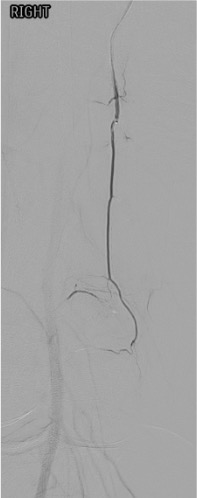

Pre-embolization selective genicular angiogram demonstrating hypertrophied vessels and synovial hypervascularity in the territory of the patient's pain.Post-embolization angiogram showing pruning of the abnormal hypervascularity with preserved flow to normal tissue — the desired endpoint.

Baseline angiography: SFA and popliteal artery runs in AP and oblique projections to identify all genicular arteries and their branching patterns.

Angiographic hyperemia / synovial blush in the symptomatic territory is the primary target. This appears as a late-phase parenchymal blush beyond the normal capsular stain.